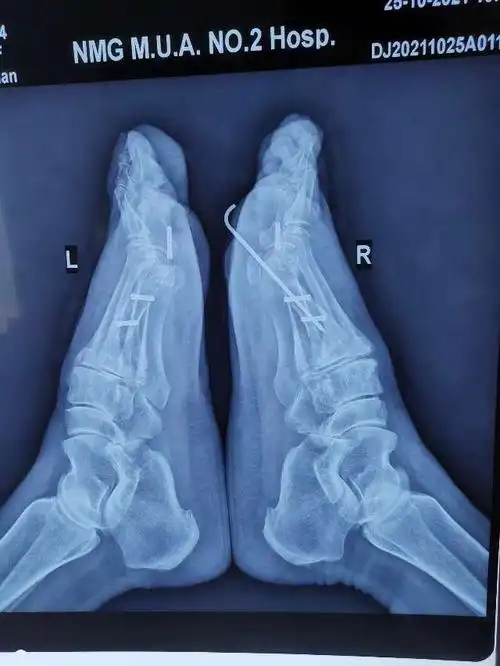

36岁双足拇外翻畸形矫正手术一例

大脚骨scarf akin截骨 - 好大夫在线